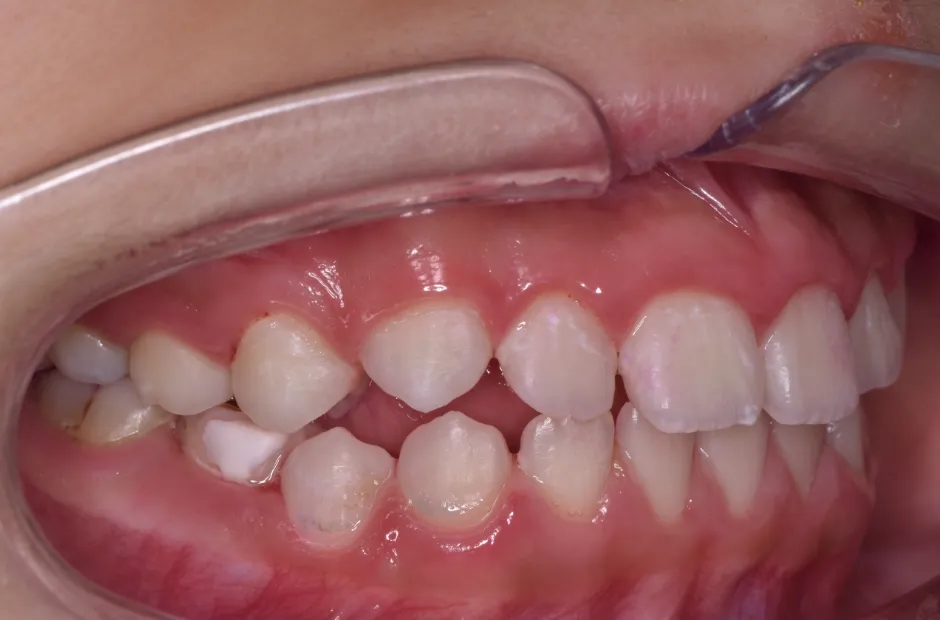

叢生

| 診断名・主訴 | 叢生 |

|---|---|

| 年齢・性別 | 10歳・女性 |

| 治療期間・回数 | 2年半 |

| 治療に用いた主な装置 | 拡大床装置 |

| 抜歯部位 | なし |

| 治療費 | 30万円(税抜) |

| リスク・副作用 | 装置による違和感・疼痛・歯肉退縮・歯根吸収・虫歯のリスクなど |

治療前